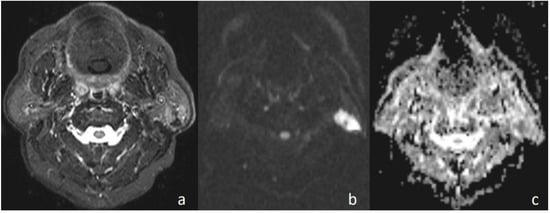

Figure 2. Pleomorphic adenoma of the parotid gland. (a) Axial T2-weighted image (T2WI) shows a mass in the left parotid gland; (b) the lesion shows low signal intensity on DWI; and (c) the mass is hyperintense on the ADC map (ADC value of 1.55 × 10−3 mm2/s).

In the current study, the mean ADC value of benign masses with high signal intensity was significantly (Figure 2) higher than that of malignant (Figure 3) masses with low signal intensity. These differences in ADC values may be explained by the differences in the histopathological characteristics of benign and malignant tumors. Generally, malignant tumors show hypercellularity and have enlarged nuclei, and hyperchromatism. These histopathological characteristics reduce the diffusion space of water protons in the extracellular and intracellular regions [13,14].